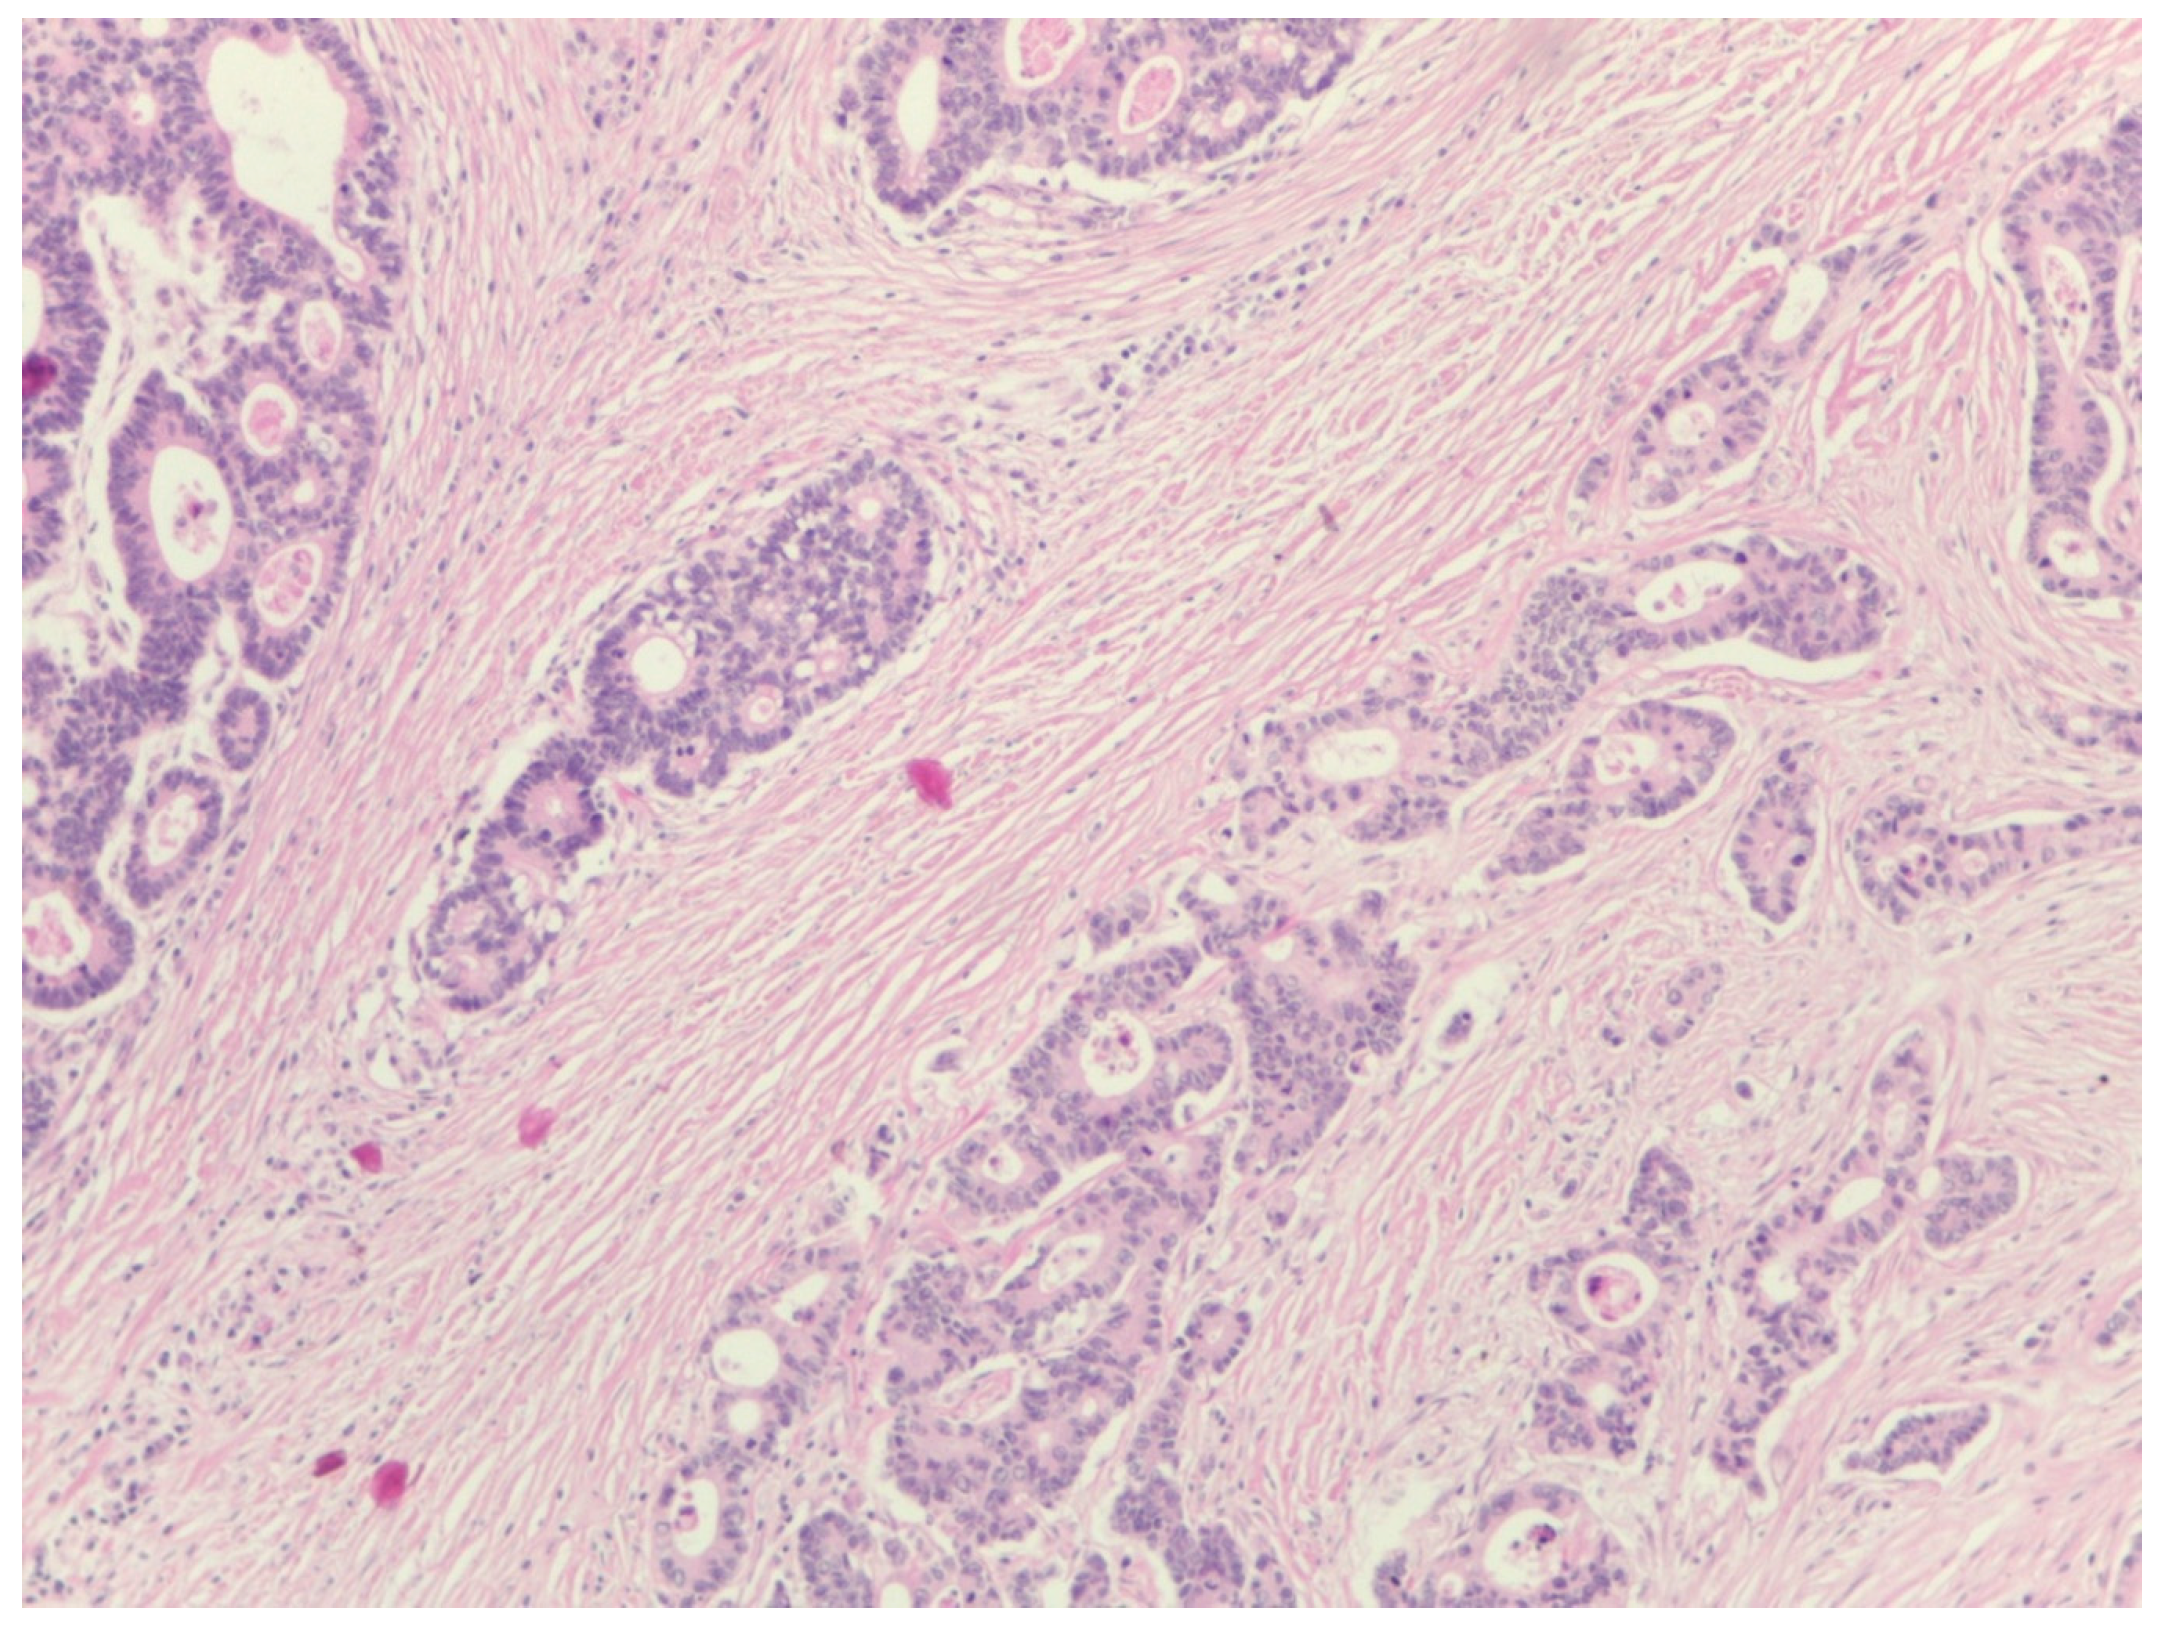

Unselective Measurement of Tumor-to-Stroma Proportion in Colon Cancer at the Invasion Front—An Elusive Prognostic Factor: Original Patient Data and Review of the Literature

2. Materials and Methods